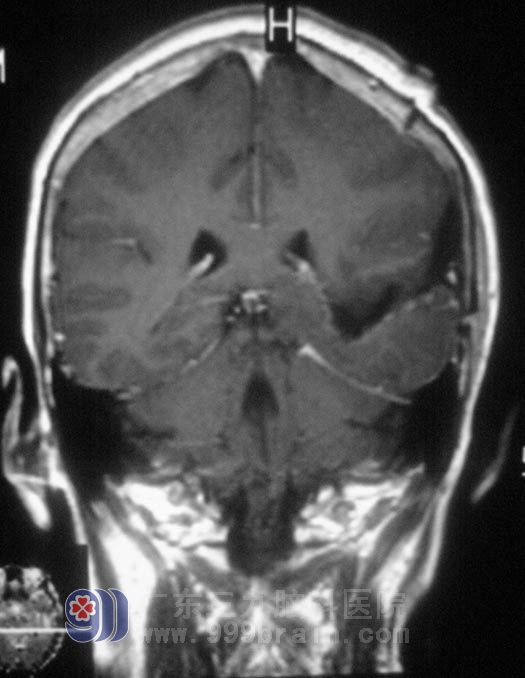

头颅CT+增强结果提示“1、左侧颞叶占位性病灶,2、CTA:左锁骨下动脉、左侧颈内动脉硬化”;头颅MRI检查结果提示:左侧侧脑室占位性病变,考虑为脑膜瘤可能性大。

11月14日,广东三九脑科医院综合神经外科 鲁明主任主刀,在全麻下行左侧脑室脑膜瘤切除术,术前导航定位,取左侧颞顶马蹄形皮瓣切口,术中见肿瘤质地中,血供一般,予肿瘤全切。术后由于语言不通,她每每见到医护人员都会竖起大拇指,似乎在说:“好,好,你们真好,城市真好……”。方奶奶恢复很快,右侧肢体麻木、乏力情况较前好转,未见有口角流涎。病理检查:(左侧侧脑室后角)脑膜瘤,WHO I级。